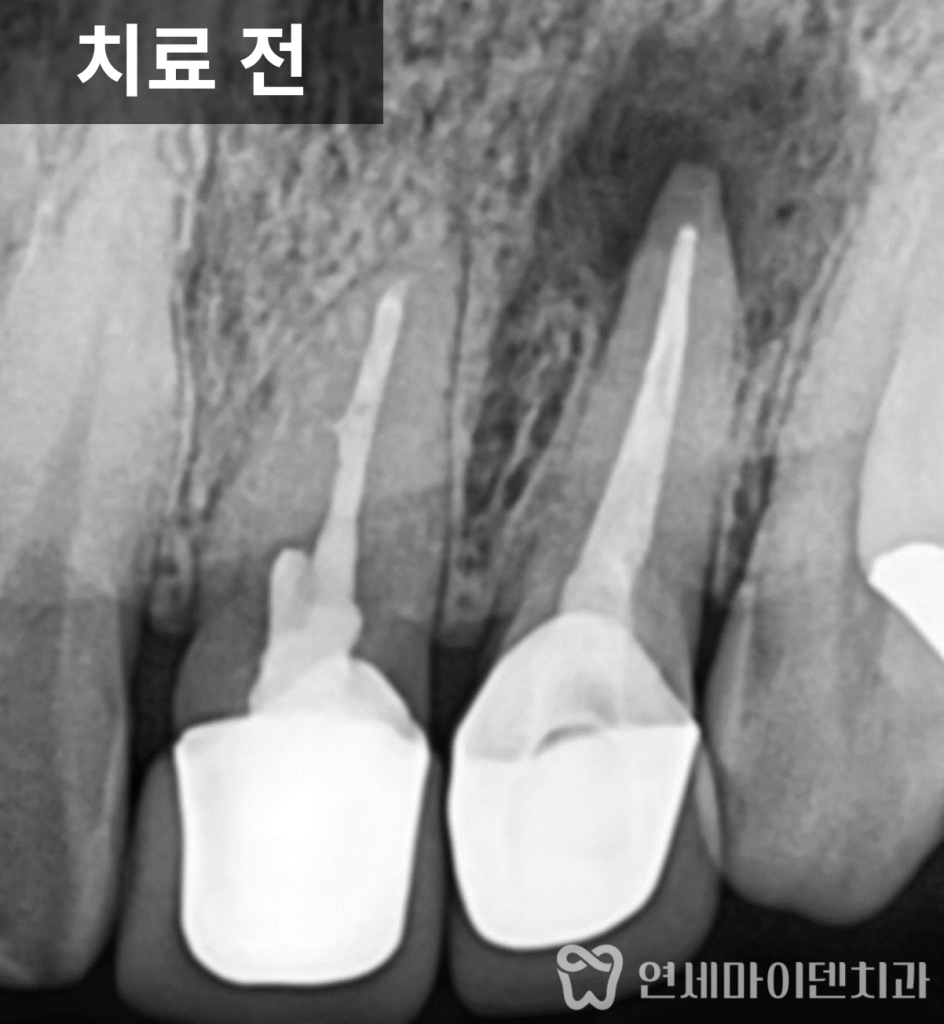

치료 전 엑스레이를 보면

앞니는 이미 신경치료 후 크라운까지

마무리된 상태였습니다.

다만 한쪽 치아의 뿌리 끝에만

둥글게 뼈가 녹아 있는

큰 염증

이 관찰되었습니다.